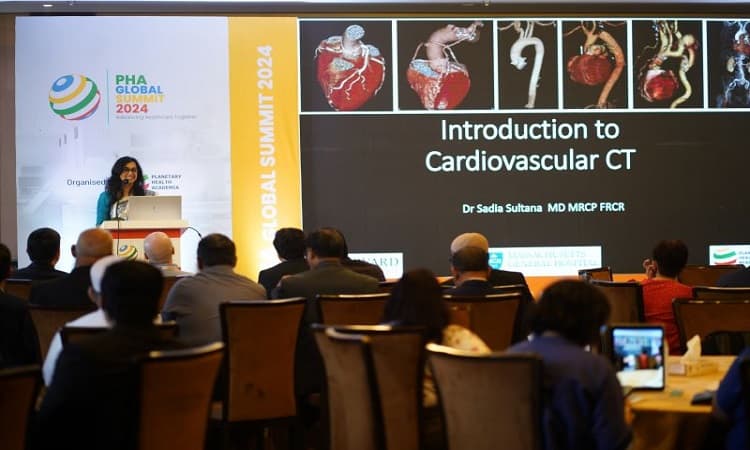

আজ ‘পিএইচএ গ্লোবাল সামিট-২০২৪’ এর উদ্বোধন

'পিএইচএ গ্লোবাল সামিট-২০২৪' উদ্বোধন করেছেন স্বাস্থ্য ও পরিবারকল্যাণ মন্ত্রী জাহিদ মালেক। এতে ২,০০০+ চিকিৎসক, গবেষক ও শিক্ষাবিদ অংশগ্রহণ করছেন। সম্মেলনে ৩০টির বেশি কোর্স ও বৈজ্ঞানিক সেশন অনুষ্ঠিত হবে।

পিএইচএ গ্লোবাল সামিট: দেশে প্রথমবারের মত হচ্ছে লন্ডন কোর রিভিউ কোর্স

পিএইচএ গ্লোবাল সামিট-২০২৪ এর অংশ হিসেবে বাংলাদেশে প্রথমবারের মতো লন্ডন কোর রিভিউ কোর্স অনুষ্ঠিত হয়। ইউনাইটেড কনভেনশন সেন্টারে ১৮-২২ ফেব্রুয়ারি কার্ডিওথোরাসিক সার্জারির সাম্প্রতিক অগ্রগতি নিয়ে আন্তর্জাতিক ও জাতীয় চিকিৎসকরা অংশগ্রহণ করেন।

ঢাকায় ২৪ ও ২৫ ফেব্রুয়ারি হচ্ছে দক্ষিণ এশিয়ার বৃহৎ স্বাস্থ্য সম্মেলন

২০২৪ সালের ফেব্রুয়ারিতে ঢাকায় অনুষ্ঠিত 'পিএইচএ গ্লোবাল সামিট-২০২৪'-এ অংশ নেন ২,০০০+ চিকিৎসক ও গবেষক। ২৪–২৫ ফেব্রুয়ারি অনুষ্ঠিত মূল পর্বে ৫০ আন্তর্জাতিক বক্তা ও ৩০টির বেশি কোর্স ছিল।

স্বাস্থ্য নিয়ে ঢাকায় হতে যাচ্ছে এশিয়ার সবচেয়ে বড় সম্মেলন2024

‘পিএইচএ গ্লোবাল সামিট-২০২৪’ ঢাকায় প্রথমবার আয়োজিত হয় ফেব্রুয়ারিতে। ৯ দিনব্যাপী এই সম্মেলনে ২০০০+ চিকিৎসক, ৫০ আন্তর্জাতিক বক্তা ও ১০০ দেশি বিশেষজ্ঞ অংশ নেন। আয়োজনে ছিল ৩০+ বৈজ্ঞানিক সেশন ও ক্যারিয়ার গাইডেন্স।